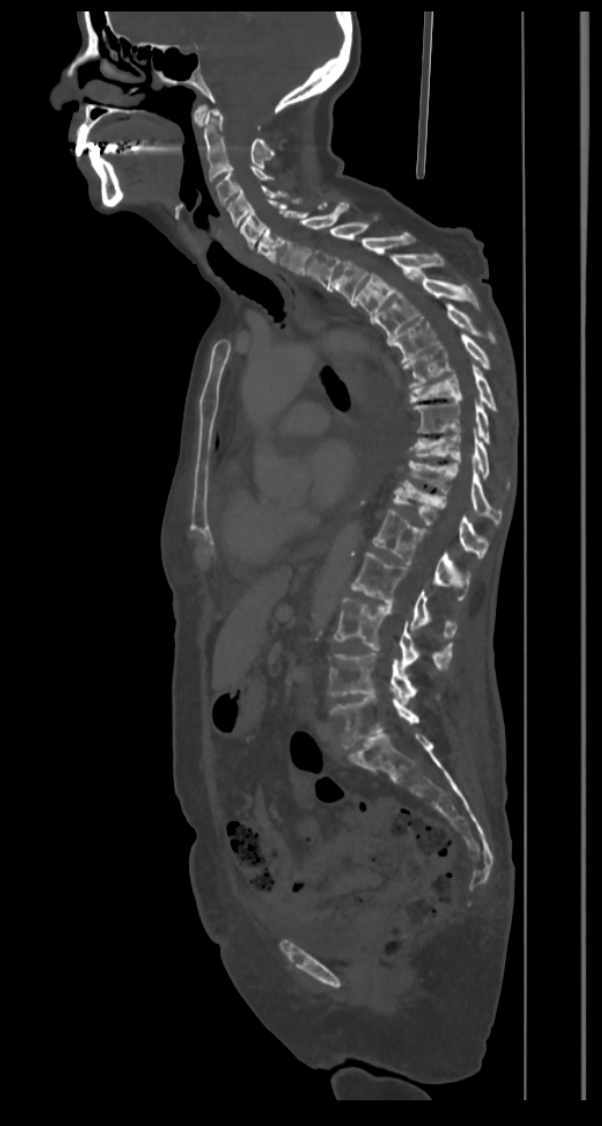

fraturas patologicas_multiplas_metas_osseas

Tomografia computadorizada (reconstrução sagital). Observam-se múltiplas lesões ósseas mistas (líticas e blásticas) acometendo a coluna cervical, torácica e lombar, compatíveis com metástases ósseas no contexto de câncer de mama. Associam-se fraturas patológicas dos corpos vertebrais de T8, T10, T11 e T12, com redução superior a 50% da altura e discreta retropulsão dos muros posteriores.